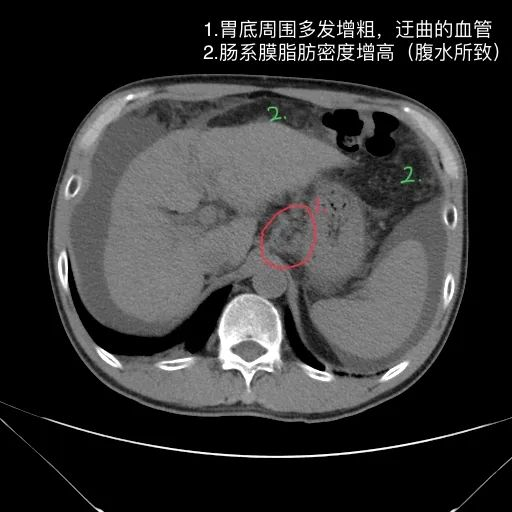

肝脏缩小,包膜凹凸不平,肝裂增宽,各叶比例失衡,肝实质密度不均,肝S4小片低密度影,约cm;胆囊不大,其内未见异常密度影,胆道系统未见扩张;胰腺、脾脏形态、密度、大小未见异常;双肾上腺及双肾形态、密度、大小未见异常,双输尿管未见扩张,膀胱充盈良好,壁光滑,其内未见异常密度影;前列腺未见异常;胃肠道未见充盈,壁未见明确增厚,食管胃底多发迂曲、增粗血管,腹部及腹膜后未见肿大淋巴结;腹水。

1.肝硬化失代偿表现(腹水,食管胃底静脉曲张)。

如上是肝硬化失代偿的典型表现。但没有门脉增宽和脾大表现。此外肝S4的小片低密度影除考虑为囊肿或镰旁假病灶外,还需警惕肿瘤?